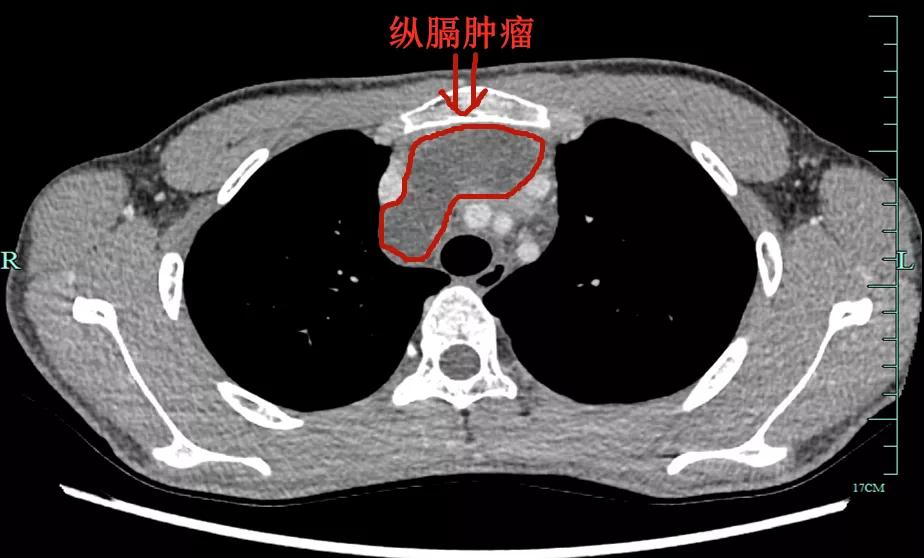

箭头所指为巨大纵隔肿瘤